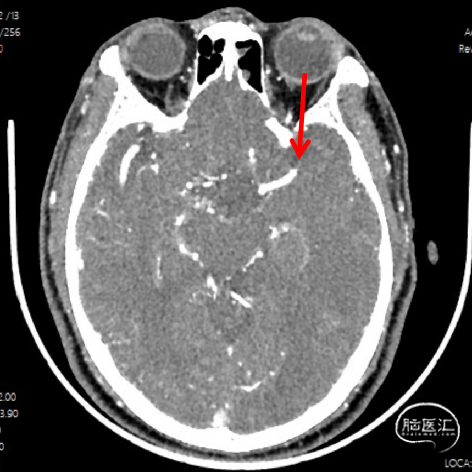

CTA

1、急性脑梗死。2、左侧大脑中动脉M1段闭塞。

ICAS合并血栓?

夹层合并血栓?

栓塞?